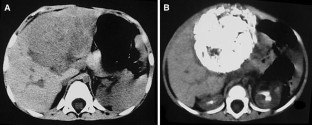

Fig. 1

Fig. 2

Fig. 3